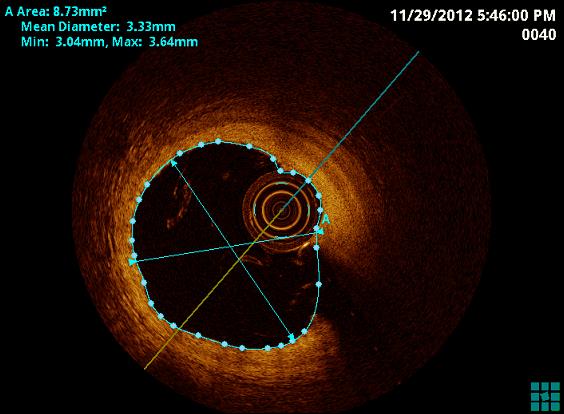

Optische Kohärenztomographie (OCT)

Die optische Kohärenztomographie (OCT) ist ein weiteres invasives bildgebendes Verfahren in der Diagnostik der koronaren Herzerkrankung. Auf Infrarotlicht basierend, ist eine hohe Auflösung biologischer Gewebestrukturen und hierdurch eine optimale und suffiziente Bildgebung der koronaren Gefäßwand möglich.

Durch die OCT können Koronarplaque mit höherer Sensivität und Spezifität erkannt und deren Beschaffenheit interpretiert werden. Durch die hohe Auflösung der OCT können im Besonderen komplexe Bifurkationsstenosen, Stenosen des Hauptstamms, oder Stenosen an mehreren Koronararterien beurteilt werden. Auch die Beurteilung der Lage und Positionierung eines Stents ist nach Implantation in hoher bildlicher Auflösung möglich und ist hier von besonderer Bedeutung.